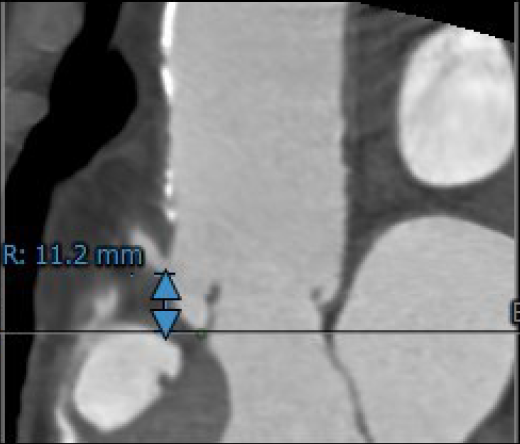

3.患者双侧冠脉开口高度可LCA:10.2mm,RCA:11.2mm;

右冠开口高度11.2mm